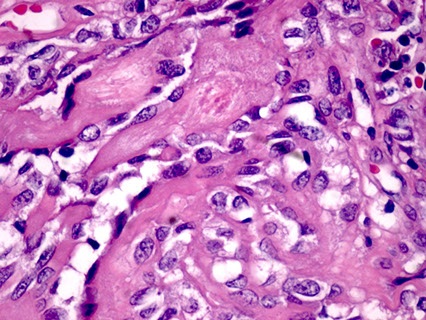

Acinic Cell Carcinoma

Malignant neoplasm with cells resembling normal serous acinar cells;

Parotids(4/5) > Submandibular > Minor salivary glands, F>M

May be bilateral or multicentric (like Warthin’s)

Tumors are generally small discrete lesions

- there is no b9 counterpart (acinic cell adenoma)

- grossly firm, circumscribed most of the time

Variable architecture (types) and cell morphology

Clear cytoplasm generally, but can be solid or vacuolated

- if cytoplasmic vacuoles present, may stain PAS (+); however they are just secretory granules and not mucin (as in MEC)

- usualy basophilic c lots of lymphoid infiltrate

- can look a little like thyroid

Can be in sheets or microcystic, glandular, follicular or papillary patterns

Usually few mitoses and little anaplasia

IHC: (+) PAS, PASD, (clear cells are PAS and mucin neg), keratin, amylase, transferrin, IgA, proline-rich protein, ANO1 (anoctamin-1)/DOG1 (Discovered On GIST-1), SOX10

- Negative GCDFP-15, MUC1, BRST-2 and mammaglobin and HER2

Clinical course dependent of degree of pleomorphism, though not well established

10-15% with LN mets, up to 35% recurrence

Both associated with worse prognosis

- otherwise fairly good 5-year survival (low-risk)